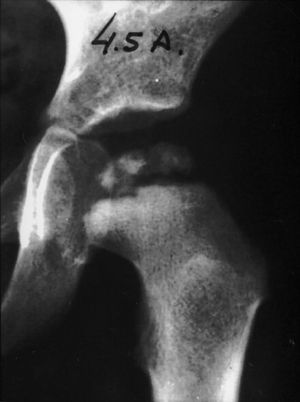

Se le realizó seguimiento hasta el final del crecimiento. En la última revisión, con 17 años de edad, el rango de movimiento fue menor que el de la cadera contralateral y la radiografía mostró una cabeza femoral irregular, clase V según la clasificación de Stulberg1 (fig. 2). Tras esta revisión, se le dio el alta definitiva.

El pronóstico funcional de los sujetos con recurrencia de la enfermedad de Legg-Calve-Perthes es generalmente malo: la cadera no tiene una conformación normal cuando se produce el segundo episodio; este segundo episodio suele ser más grave, la edad es más avanzada y, por tanto, también es menor la capacidad de remodelación. Quizás por todas estas razones al final del desarrollo estos sujetos presentan una cadera elíptica y aplanada. En el caso aquí descrito, tras el primer episodio el niño presentaba una cabeza femoral clase I según la clasificación de Stulberg1 y posteriormente (al final del desarrollo) presentaba una cabeza femoral clase V, con cambios degenerativos, elíptica e incongruente, subluxada y en bisagra (fig. 2).